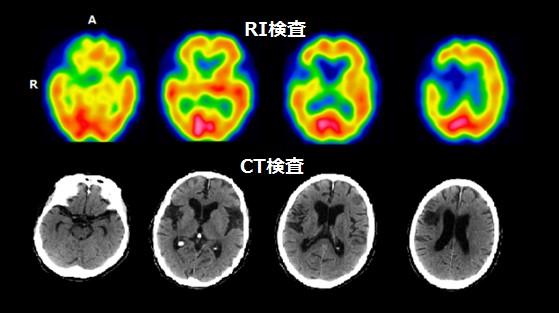

【脳血流検査】

脳血流検査では、脳血管の狭窄や認知症などで、脳内の血流が低下した部位を画像化する検査です。